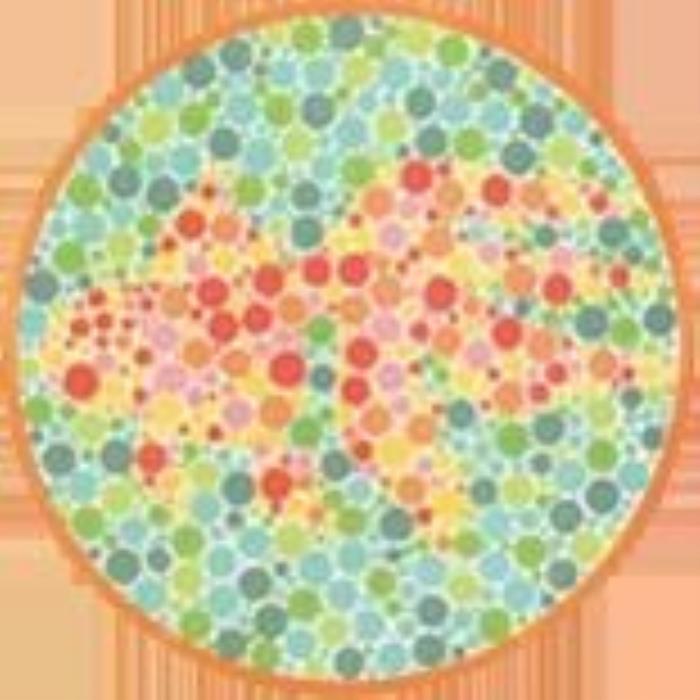

终极测试!!下面这张图你看到了什么数字?

结果:

左图:全色弱者及正常者读不出来,红绿色盲者及红绿色弱者大多能看到5

右图:正常者及全色弱者大多找不到,红绿色盲者及红绿色弱者容易找到

欢迎大家来评论一起猜一猜!